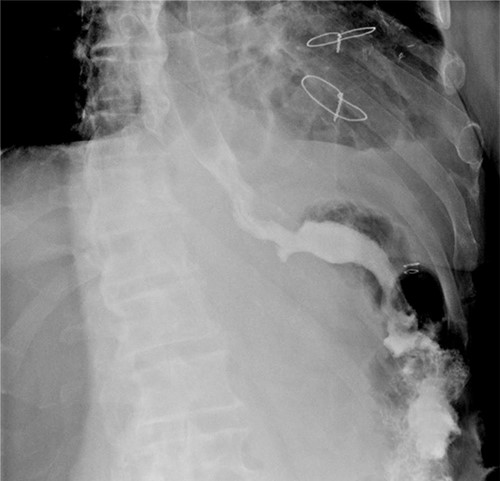

A linear semi-mechanical latero-jejunal jejuno-jejunal anastomosis was performed at 60 cm from the oeso-gastric anastomosis (Fig. 5). The mesenteric space and Petersen’s space were closed using non-resorbable stitches. The spleen and the stomach were removed by a Pfannenstiel incision. A drain was left in place near the oeso-jejunal anastomosis. An oeso-jejunal transit was performed at the fifth post-operative day, which showed no signs of leakage (Fig. 6). The progressive oral alimentation was resumed.

Intraoperative image that reveals the confection of oeso-jejunal anastomosis.